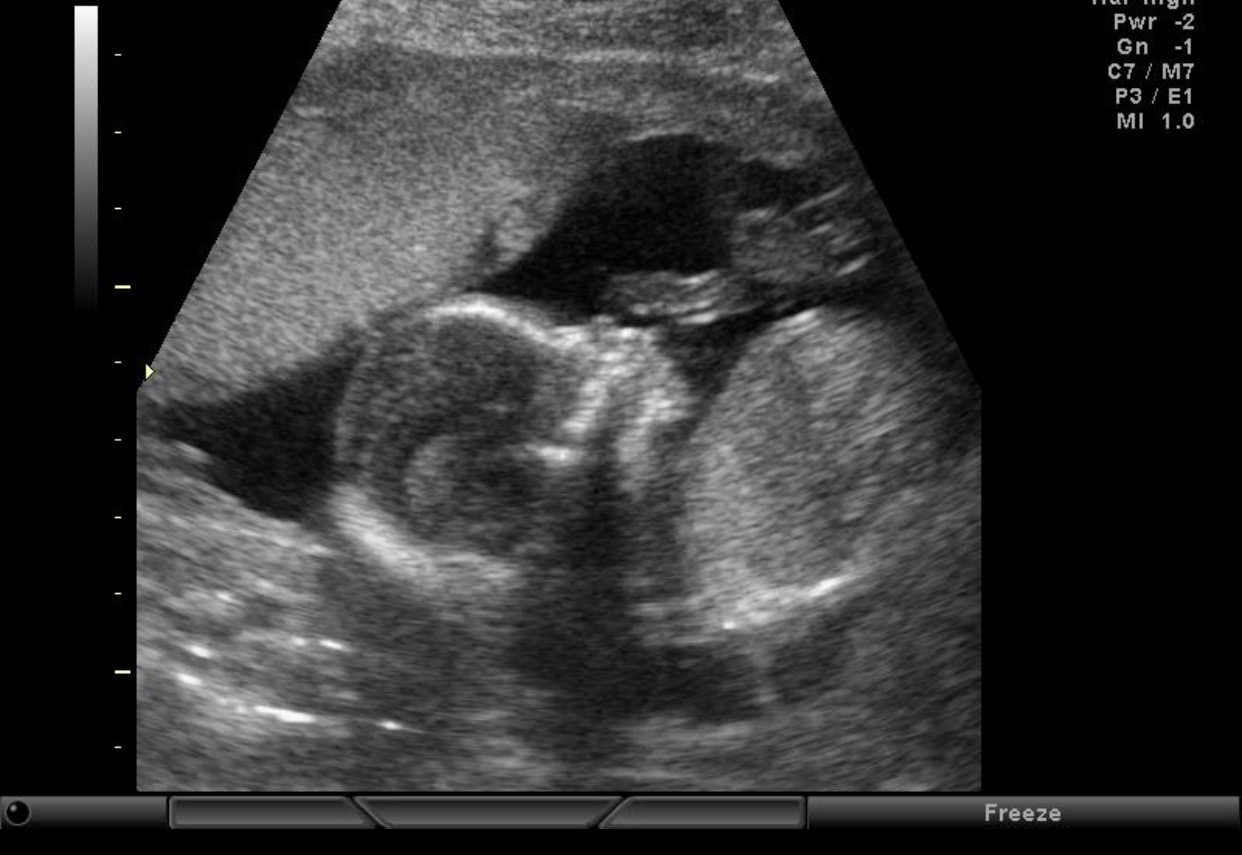

Everyone on my pregnancy app thinks this is a boy due to the skull. Any possibility of girl still?? After 4 boys, I am praying! The cord was between the legs the whole time so we didn't get a nub look or picture :( 12 weeks and 5 days